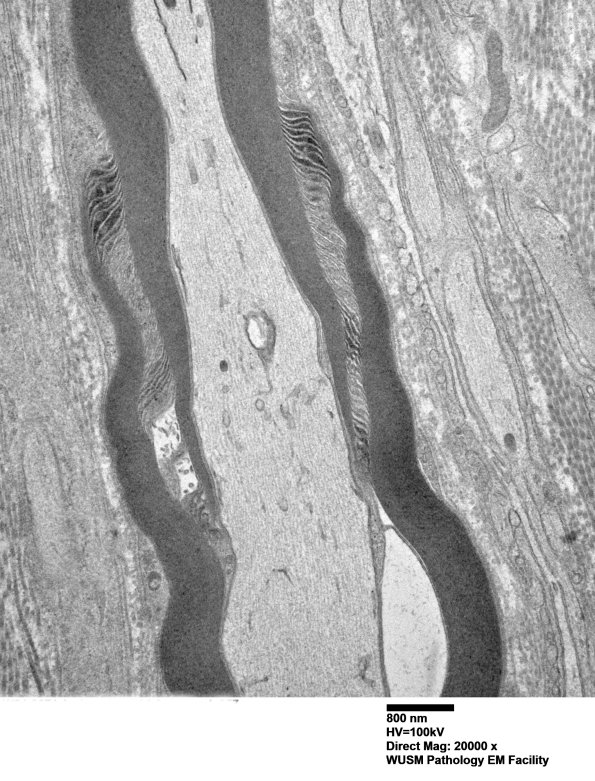

Washington University Experience | PERIPHERAL NEUROPATHY | 3 NORMAL MYELIN & SCHWANN CELLS | 3 Schmidt-Lanterman Clefts | 2A2 W24-3671 Anders G (Case 2) Sural_057 - Copy

2A2-5 Multiple magnifications of the SLC of this axon. Notice the variation in the constituent cytoplasm within leaflets of the SLC ranging from dense granular content to pale lucent cytoplasm. (Electron micrographs)